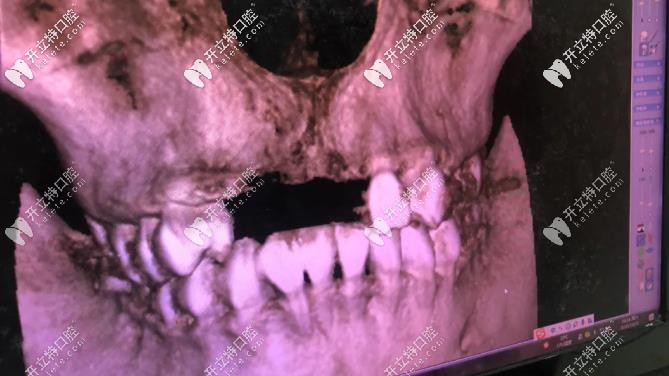

▼這個全景影像檢查可快,幾分鐘就出來▼

全景影像檢查可快,幾分鐘就出來

由于我長期帶假牙,牙骨頭薄,后期種牙手術(shù)難度較大;唯美口腔:彭參醫(yī)師在牙齒缺失修復(fù)、復(fù)雜種植這方面很擅長,就找的他,(我家人目標(biāo)很明確的,對癥下藥)。

1年多點完成種植,之前缺牙時間長,再加上長期戴假牙,彭醫(yī)生:說我的骨頭比較薄(正常種牙厚度:6.5-7毫米,我骨厚度就:3毫米),所以要增量骨組織;我是四顆門牙缺失,種2顆植體,然后戴四連冠就好;現(xiàn)在明白,做種植牙,并不是缺幾顆種植牙幾顆。